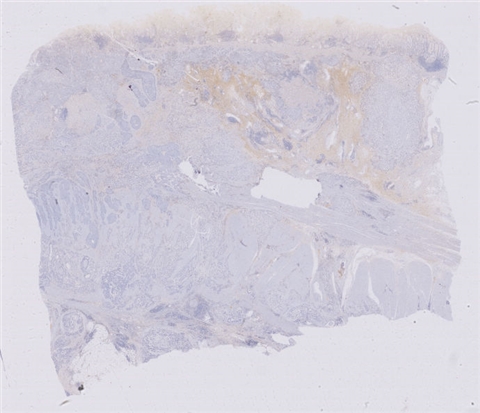

案例8 (6967)

性别:       年龄:69

患者详情: 患者因上腹部疼痛1年余,2020年05月19日于我院行胃镜检查示:胃窦部可见一巨大溃疡,底深凹,覆白苔,周围堤坝状,活检弹性可。

大体所见: 送检远端胃:小弯侧长8cm,大弯侧长16cm,临床已沿大弯侧剪开,距下切端4cm处小弯侧见一溃疡,大小1.8X1.5X00.3cm,切开切面灰白质韧,黏膜层与肌层游离。

医院: 南昌大学第一附属医院